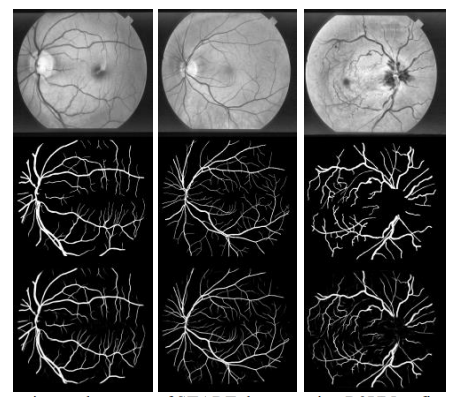

为了证明RU-Net和R2U-Net模型的性能,我们在三个不同的医学影像数据集上对它们进行了测试。这些包括从视网膜图像中分割血管(如图6所示的DRIVE、STARE和CHASE_DB1)、皮肤癌病灶分割和2D图像中的肺分割。对于这个实现,Keras和TensorFlow框架在一台拥有56G RAM和NIVIDIA GEFORCE GTX-980 Ti的GPU机器上进行实验。

1)血管分割

我们在三种不同的视网膜血管分割数据集上进行了实验,包括DRIVE、STARE和CHASH_DB1。驱动数据集由40幅彩色视网膜图像组成,其中20幅用于训练,其余20幅用于测试。每个原始图像的大小为565×584像素[44]。为了开发一个方形数据集,图像被裁剪成只包含第9列到第574列的数据,这使得每个图像都有565×565像素。在这个实现中,我们考虑了从驱动器数据集中的20个映像中随机选择的190000个图像块,其中171000个图像块用于培训,剩下的19000个图像块用于验证。对于图7所示的所有三个数据集,每个图像块的大小都是48×48。第二个数据集STARE包含20个彩色图像,每个图像的大小为700×605像素[45,46]。由于样本数量较少,因此经常使用两种方法对该数据集进行训练和测试。首先,训练有时是从所有20幅图像中随机选取样本[53]。

另一种方法是“leave-one-out”方法,即对每个图像进行测试,并对剩余的19个样本进行训练[47]。因此,训练和测试之间没有重叠。在这个实现中,我们对STARE数据集使用了“leave-one-out”方法。CHASH_DB1数据集包含28个彩色视网膜图像,每个图像的大小为999×960像素[48]。该数据集中的图像采集自14名学龄儿童的左右眼。数据集被分成两组,其中样本是随机选择的。20个样本集用于培训,其余8个样本用于测试。

由于输入数据的维数大于整个驱动器数据集,我们考虑了STARE和CHASE_DB1的20个图像中总共250000个补丁。在这种情况下,225000个补丁用于培训,其余25000个补丁用于验证。由于二进制FOV(如图6第二行所示)不适用于STARE和CHASE_DB1数据集,因此我们使用类似于[47]中描述的技术来生成FOV掩码。基于补丁的方法的一个优点是,补丁允许网络访问像素的局部信息,这对整体预测有影响。此外,它确保输入数据的类是平衡的。在整个图像上随机地对输入面片进行采样,整个图像还包括视场的外部区域。

1)利用DRIVE数据集对视网膜血管进行分割。

用所提出的R2U网络模型实现的精确分割结果如图8所示,图9和10显示使用驱动器数据集时的培训和验证精度。这些图表明,与U-Net和ResU-Net相比,提出的R2U-Net和RU-Net模型在训练和验证阶段都提供了更好的性能。

2) STARE数据集上的视网膜血管分割

使用STARE数据集时R2U网络的实验输出如图11所示。STARE数据集的训练和验证精度如图所示。分别是12和13。

在R2U的训练中,它的表现比所有其他型号都要好。此外,图13中的验证精度表明,与等效的UNet和ResU-Net模型相比,RU-Net和R2U-Net模型提供了更好的验证精度。因此,性能证明了所提出的分割任务方法的有效性。